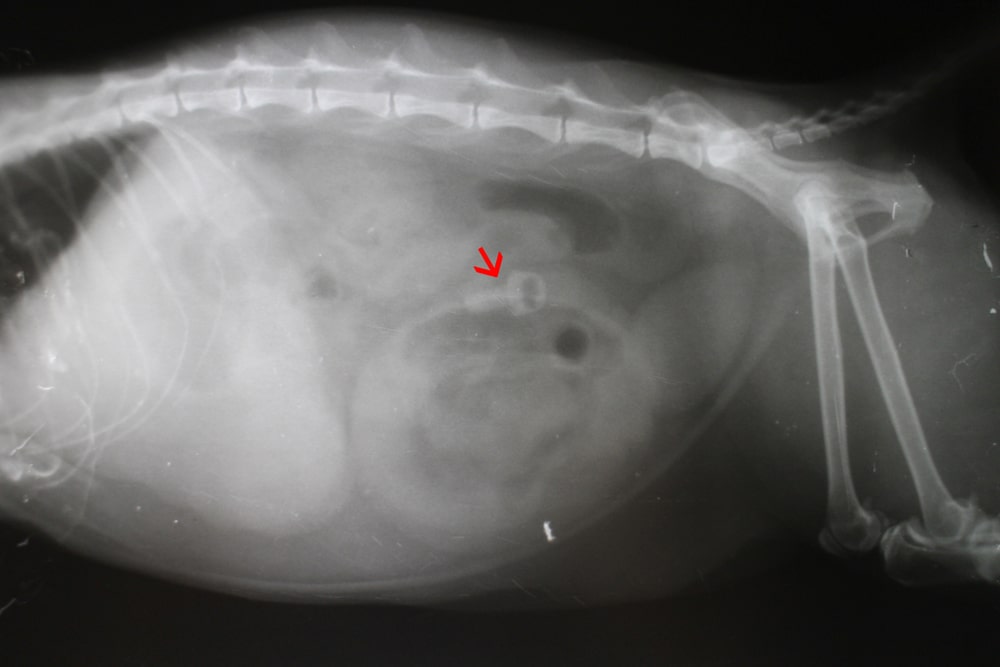

就診對象:

一隻 10 個月大的長毛米克斯貓,名叫 Casper。

就診原因:

Casper 出現嘔吐,嘔吐物裡有黏稠的飼料。飼主懷疑牠在幾天前吞下了一根約 5 公分長的縫衣針。

臨床檢查:

在醫院的問診與身體檢查中,發現 Casper 食慾變差,也比平常安靜。

X 光顯示那根縫衣針已經跑到胸腔位置,而且是垂直穿過食道壁。

治療方式:

醫師在全身麻醉下替 Casper 做內視鏡,想辦法把縫衣針取出並檢查食道狀況。

內視鏡看到縫衣針是和縫線一起被吞下去的,整根針都穿進食道壁裡,只剩下一點點縫線露在食道裡面。

醫師先拉動那段小縫線,把縫衣針拉回食道裡,再用內視鏡的鱷魚夾把縫衣針和縫線一起取出。

治療結果:

成功取出後給予抗生素與止吐藥,協助食道恢復並減輕不適。